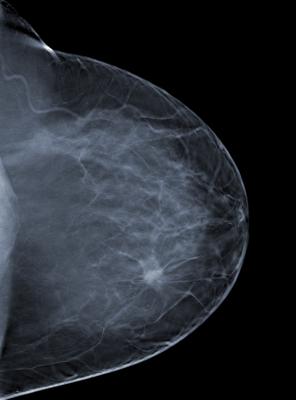

First introduced by Congresswoman Rosa DeLauro, the bill ensures that relative breast density is included in the information provided to women and health care providers following a mammogram. Studies have shown that women with dense breast tissue are at least four times more likely to develop breast cancer, and they are also more likely to have an inaccurate mammogram reading.

Gamma Medica develops, markets and services molecular breast imaging systems to help radiologists detect early stage cancers. The company utilizes molecular breast imaging, a secondary diagnostic tool that enables and improves assessments, especially for women with dense breast tissue.